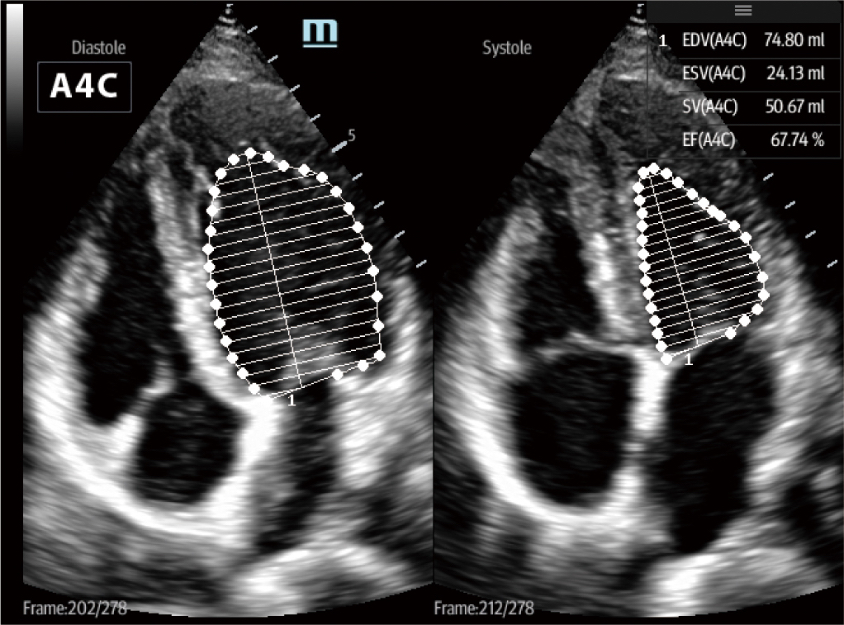

DespuĂ©s de la incubaciĂłn de COVID-19, el virus invasivo causarĂa da?o pulmonar, lo que eventualmente resultarĂĄ en insuficiencia respiratoria y conducirĂĄ a la disfunciĂłn circulatoria y multiorgĂĄnica. El TE7 ACE equipado con funciones profesionales de evaluaciĂłn pulmonar y prejustes de pulmĂłn, como?Smart VTI, Smart B-line, AutoEF, TDI?etc., puede ayudar de manera eficiente al mĂ©dico a controlar el perfil cardĂaco y el estado de los lĂquidos durante el procedimiento terapĂ©utico clĂnico.